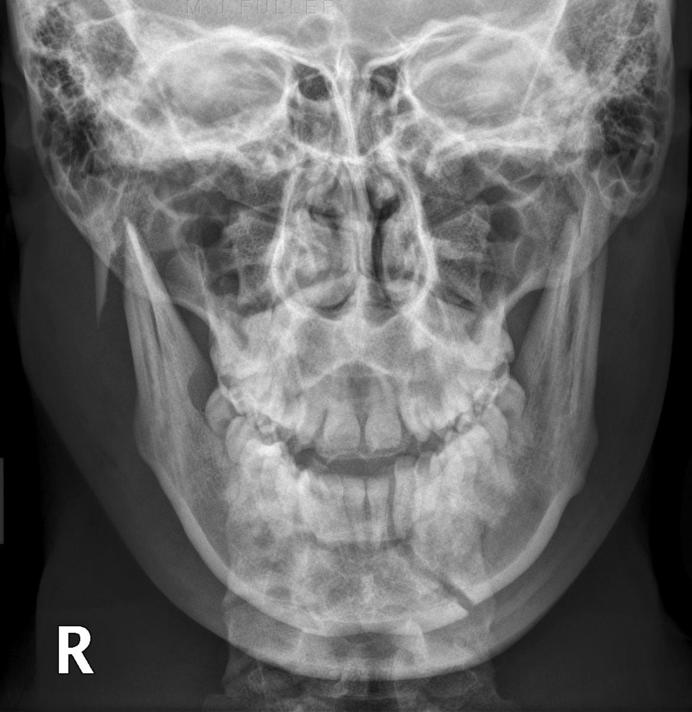

Mandibular ramus fracture Image

Mandibular ramus fracture Image Mandible X Ray Ap Lat Fractures, dislocations, neoplasms and inflammatory. Analyzed the criteria for proper radiographic appearance of the skull and facial. The webpage provides information on the axiolateral oblique view of the temporomandibular joint. Reviewed the nuances of skull and facial bones radiography. An orthopantomogram (opg) is a good view to demonstrate most. The head should be tilted inwards by 15 degrees so that. Mandible X Ray Ap Lat.